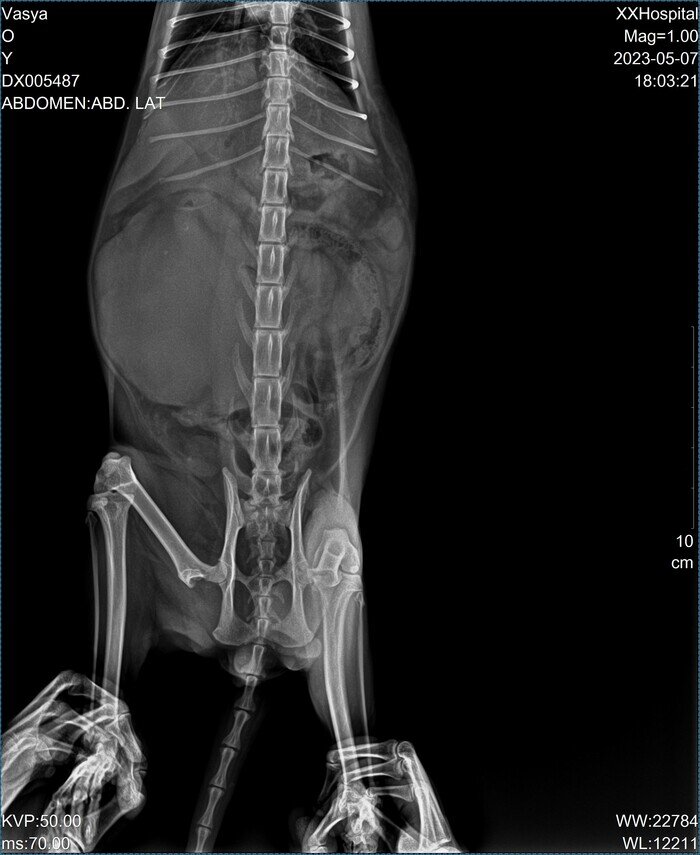

Сегодня моего кота приезжал посмотреть знакомый ветврач и с казал что его надо срочно везти в ветклинику и делать ему рентген в боковой проекции и анализы крови. Сказал что у него правая почка увеличена в размерах раз в пять. Предположительный диагноз: Гидронефроз почки? Отвез на рентген. Вот два снимка которые сегодня ему сделали. Рентгенолог говорит что на снимках она ничего не видит, кроме того что правая почка сильно увеличена в размере и ему надо делать еще и узи! В этой клинике где я был сегодня узи нет. Сделали ему общий анализ крови и анализ на биохимию. Результаты анализов крови будут готовы только завтра вечером. Говорит, рентгенолог что, скорее всего, проблему у кота придется решать только хирургическим путем и эта операция может стоить от 100 тыс. руб. Гарантий при этом совсем никаких нет! Кому-нибудь приходилось лечить похожее у котов или кошек? ЗЫ. Коту примерно 2, 5 года (точно не знаю так как взял его уже почти взрослым с улицы). У меня он живет полтора года. ЗЫ. ЗЫ. На

Отвез на рентген. Вот два снимка которые сегодня ему сделали.

Рентгенолог говорит что на снимках она ничего не видит, кроме того что правая почка сильно увеличена в размере и ему надо делать еще и узи! В этой клинике где я был сегодня узи нет.